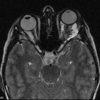

Ecchordosis Physaliphora

Cystic lesion in the prepontine cistern without enhancement or restricted diffusion extending into bone.

Absence of enhancement or restricted diffusion together with non-aggressive bony margins in this location is typical of a retroclival ecchordosis physaliphora, a notochord remnant.

Ecchordosis physaliphora is a congenital benign hamartomatous lesion derived from notochord remnants, usually located in the retroclival prepontine region, but can be found anywhere from the skull base to the sacrum.

Unlike chordomas which are often symptomatic due to brainstem or cranial nerve compression, patients with ecchordosis physaliphora are usually asymptomatic. They are found in ~2% of autopsies 1.

Ecchordosis physaliphora arise from remaining notochord cells along the axis of the spine after embryogenesis. Unfortunately, ecchordosis physaliphora and chordoma are histologically indistinguishable, other than by examining the margins, the latter demonstrating infiltrative growth.